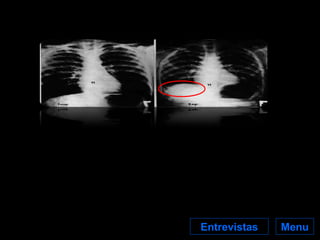

Perigos para a Saúde Menu O perigo do amianto reside essencialmente na possibilidade da inalação das suas fibras que podem alojar-se nos pulmões, onde podem permanecer durante anos. O nosso organismo reconhece-as como um “corpo estranho” e reage tentando eliminá-las através das suas células de defesa que, com o objectivo de destruir as fibras, libertam determinadas substâncias.   Estas substâncias, além de se mostrarem incapazes de eliminar as fibras, agridem os pulmões e daí podem surgir várias doenças que podem resultar inclusivamente em cancro do pulmão. Próximo

Perigos para a Saúde Menu Cerca de 85% do cancro do pulmão no homem e 65% do cancro do pulmão na mulher são causados pelo fumo do tabaco. A segunda causa de cancro do pulmão passa pela  exposição a amianto , ou pela exposição a substâncias radioactivas. Próximo

Perigos para aSaúde Menu Cerca de 85% do cancro do pulmão no homem e 65% do cancro do pulmão na mulher são causados pelo fumo do tabaco. A segunda causa de cancro do pulmão passa pela exposição a amianto , ou pela exposição a substâncias radioactivas. Próximo